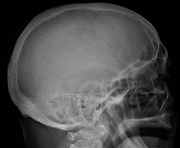

Bone pain affects almost 70% of people with multiple myeloma and is one of the most common symptoms.[2]:653[22] Myeloma bone pain usually involves the spine and ribs, and worsens with activity. Persistent, localized pain may indicate a pathological bone fracture. Involvement of the vertebrae may lead to spinal cord compression or kyphosis. Myeloma bone disease is due to the overexpression of receptor activator for nuclear factor κ B ligand (RANKL) by bone marrow stroma. RANKL activates osteoclasts, which resorb bone. The resultant bone lesions are lytic (cause breakdown) in nature, and are best seen in plain radiographs, which may show "punched-out" resorptive lesions (including the "raindrop" appearance of the skull on radiography). The breakdown of bone also leads to the release of calcium ions into the blood, leading to hypercalcemia and its associated symptoms.[23]

The diagnostic examination of a person with suspected multiple myeloma typically includes a skeletal survey. This is a series of X-rays of the skull, axial skeleton, and proximal long bones. Myeloma activity sometimes appears as "lytic lesions" (with local disappearance of normal bone due to resorption) or as "punched-out lesions" on the skull X-ray ("raindrop skull"). Lesions may also be sclerotic, which is seen as radiodense.[70] Overall, the radiodensity of myeloma is between −30 and 120 Hounsfield units (HU).[71] Magnetic resonance imaging is more sensitive than simple X-rays in the detection of lytic lesions, and may supersede a skeletal survey, especially when vertebral disease is suspected. Occasionally, a CT scan is performed to measure the size of soft-tissue plasmacytomas. Nuclear Medicine Bone scans are typically not of any additional value in the workup of people with myeloma (no new bone formation; lytic lesions not well visualized on nuclear bone scan).

Skull X-ray showing multiple lucencies due to multiple myeloma